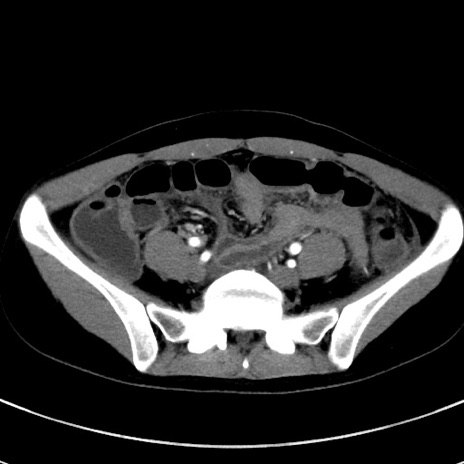

症例17(横断像)

【症例】20歳代女性

【主訴】嘔吐、下腹部痛

【現病歴】昨日夕食後に嘔吐し下腹部痛が出現。本日になっても嘔吐持続し改善しないため来院。

【身体所見】意識清明、BT 37.2℃、BP 108/67mmHg、腹部:平坦、やや硬、下腹部正中から右にかけて圧痛あり、反跳痛軽度あり、tapping pain(+)。

【データ】WBC 13600、CRP 14.94